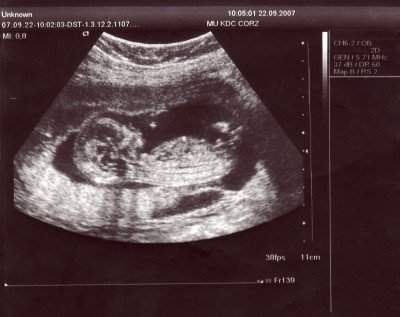

- ultrazvukové vyšetření - provádí se obvykle ve 12. až 13. týdnu, nejpozději při stáří těhotenství 13+6, nejdůležitější částí vyšetření je měření šíjového projasnění (viz dále), kromě toho lékař zhodnotí stáří plodu, uložení placenty, množství plodové vody, prohlédne končetiny a vnitřní orgány plodu.

Všechny plody na konci 1. trimestru mají na zátylku oblast, kde se hromadí tekutina. U plodů s Downových syndromem a jinými chromozomálními odchylkami je tato oblast zpravidla větší než u zdravých plodů a její měření je proto dobrým ukazatelem rizika těchto odchylek. Plody s Downovým syndrom často vykazují i jiné znaky postižení, např. chybějící nosní kůstku, kratší stehenní kosti nebo srdeční vady, ale ty jsou pouze pomocnými ukazateli při nejednoznačném výsledku měření šíjového projasnění.

Měření vyžaduje kromě kvalitního ultrazvukového přístroje také určité zkušenosti a měli by jej proto provádět pouze akreditovaní lékaři, jejichž seznam naleznete na stránkách The Fetal Medicine Foundation (z nabídky vyberte Czech Republic). Vyšetření je prozatím možné podstoupit pouze v některých nemocnicích v Česku, ostatní nemocnice nabízejí těhotným tzv. tripple test prováděný ve 2. trimestru těhotenství.